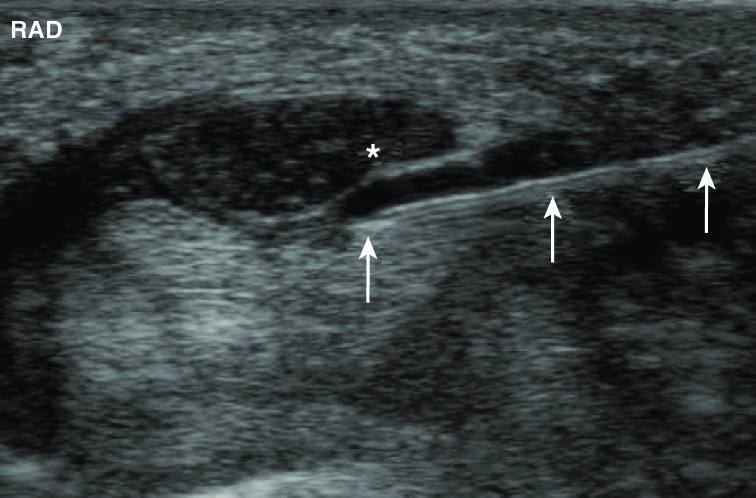

Ultrasons túnel carpico

A hidrodissecação do nervo com plasma rico em plaquetas para a síndrome do túnel do carpo não envolve o corte do ligamento, nem envolve uma cirurgia aberta e invasiva.

O plasma rico em plaquetas contém fatores de crescimento concentrados a partir das próprias plaquetas do paciente e é injectado em redor do nervo.

Na nossa experiência, isso liberta o nervo comprimido, reduz a inflamação e melhora o fluxo sanguíneo para a área – tudo isto sem prejudicar a delicada biomecânica do pulso, que é inevitável com a cirurgia de libertação do túnel do cárpico.